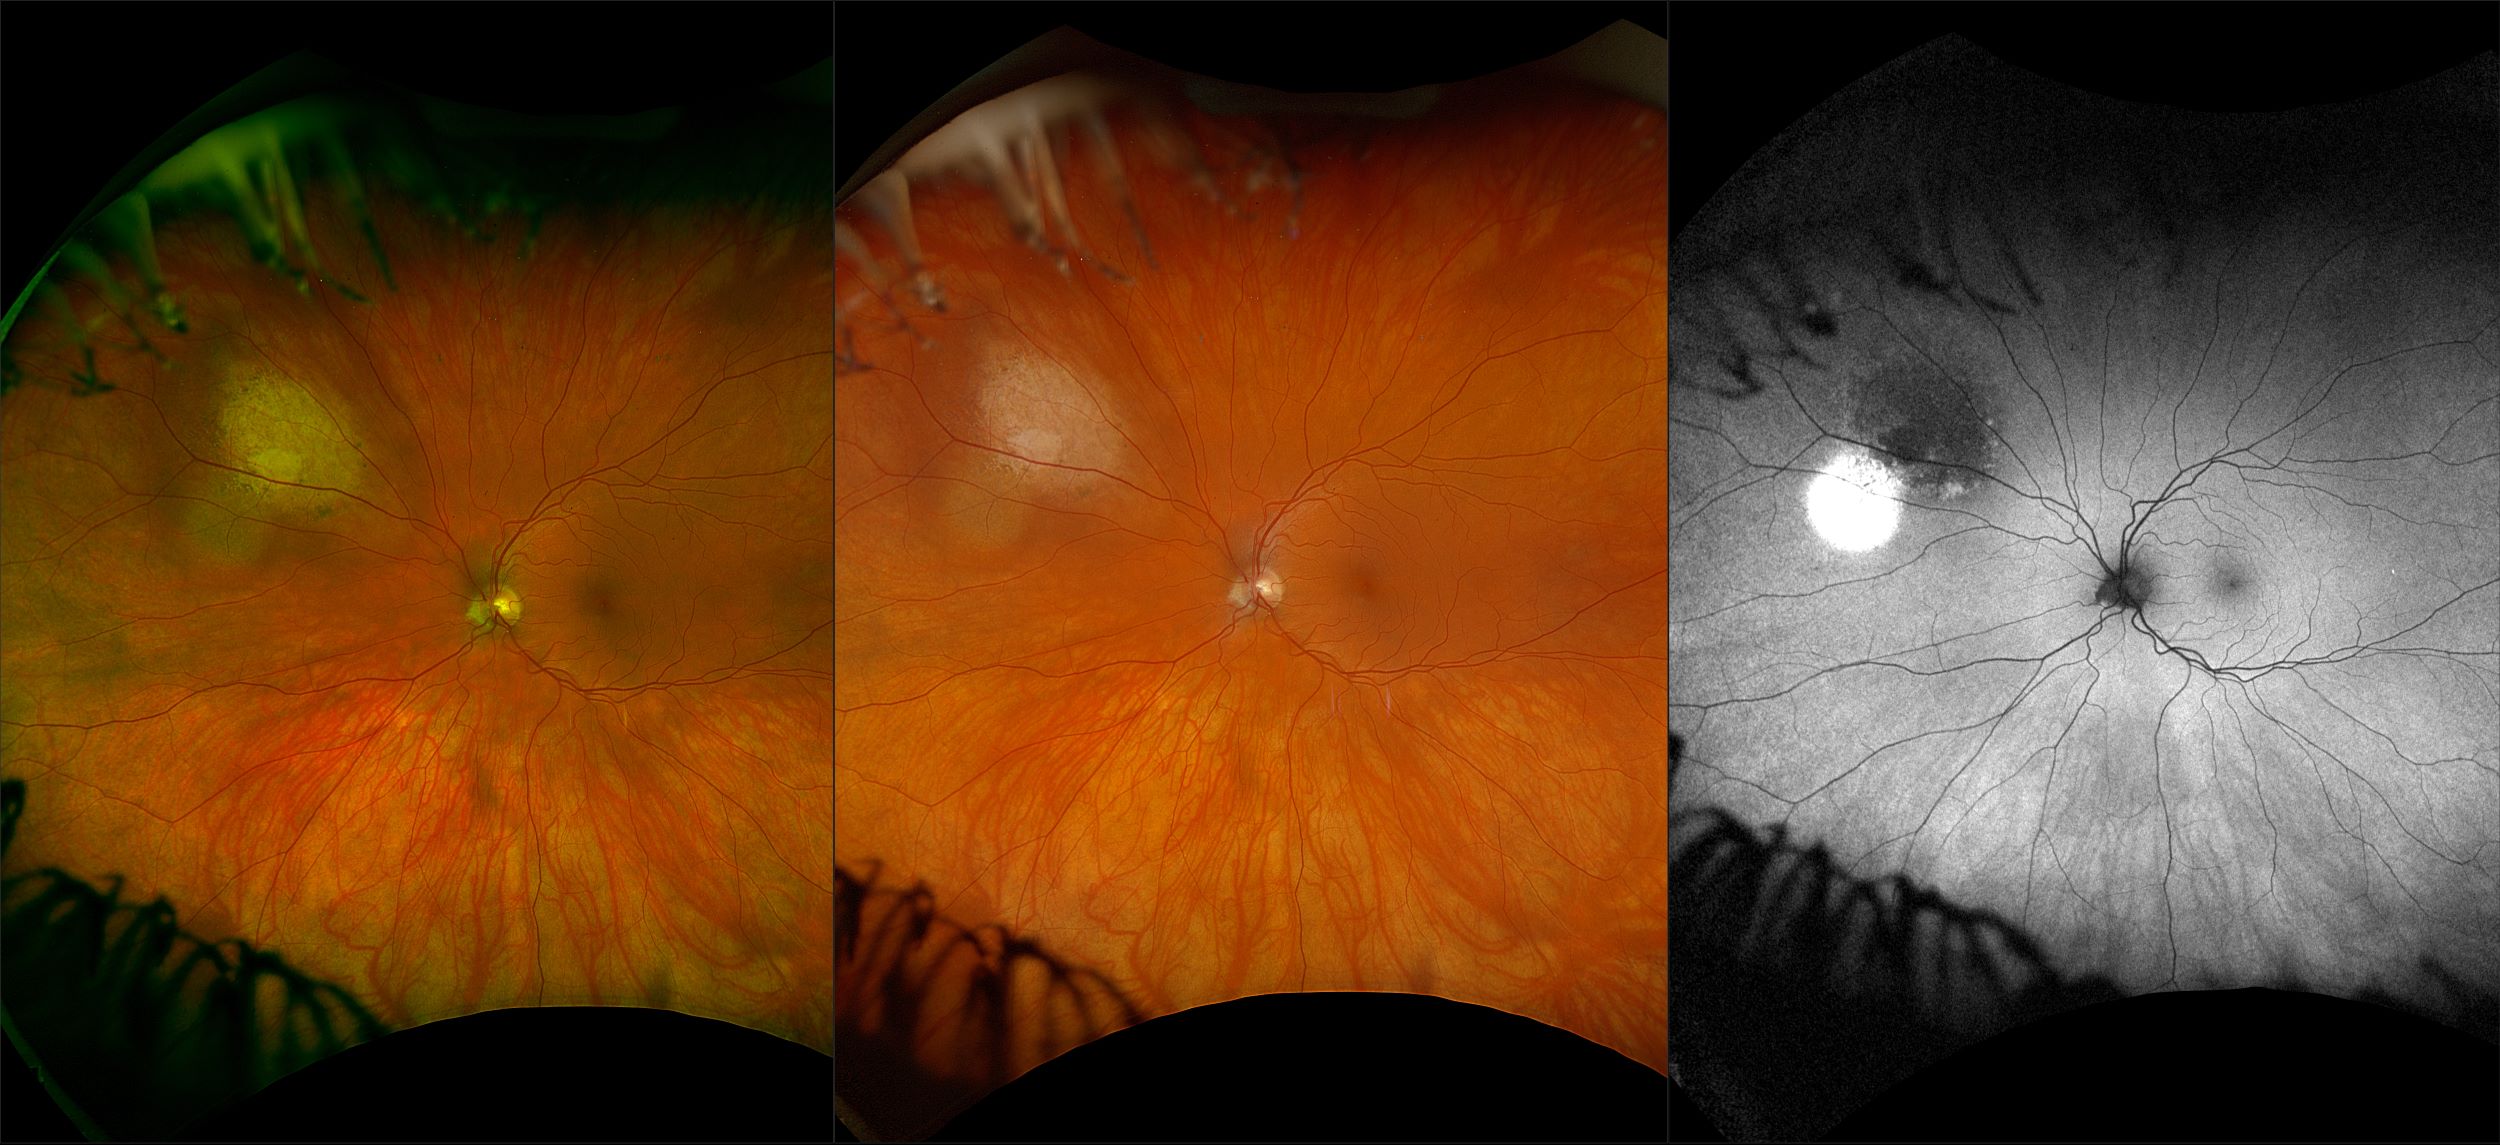

California - Choroidal Nevus, RG, AF

A choroidal nevus is simply an accumulation of melanocytes in the choroid. They are a space occupying mass or a benign melanoma. Choroidal nevi are slate gray in color, have indistinct margins, and may be slightly elevated (1-2 diopters). Since they are in the choroid, they are usually only seen in the red separation and not the green. The green separation may show the RPE degeneration associated with nevi which is seen as pigment mottling and drusen.